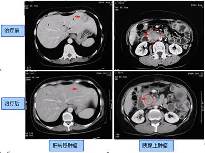

解放军三O七医院CTC肿瘤生物治疗中心(以下简称中心)自1997年就开始从事肿瘤的免疫治疗,是获得中国人民解放军总后卫生部批准、具有合法资质开展肿瘤细胞与基因治疗的临床科室,拥有1600平方米并通过GMP认证的标准GMP实验室,也是全军的肿瘤治疗中心。